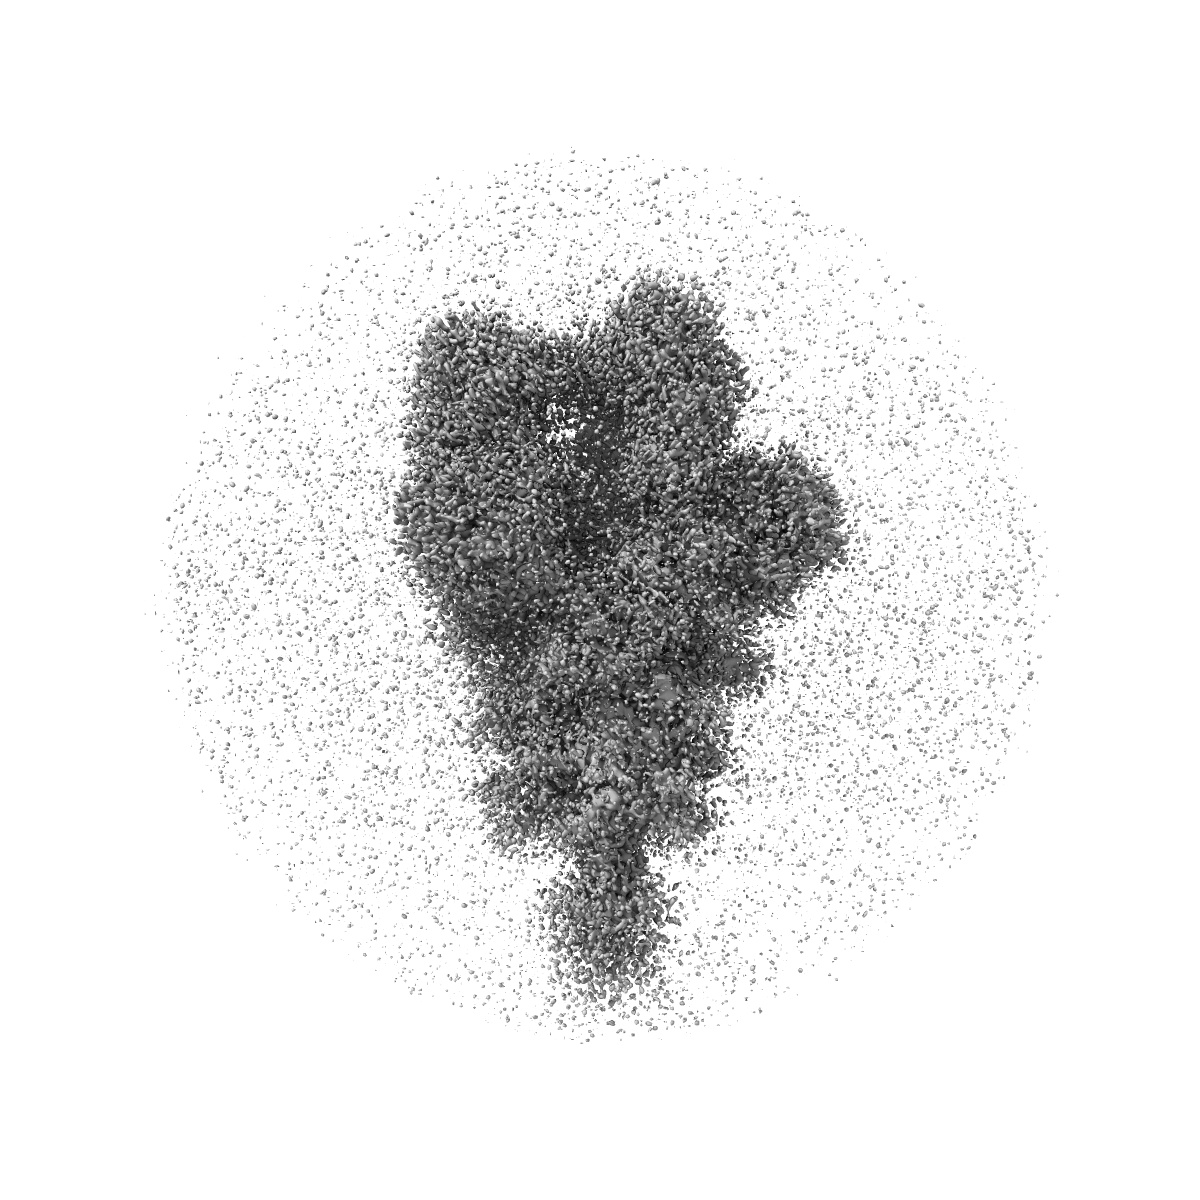

SARS-CoV-2 Spike in complex with the neutralizing antibody Cv2.3194

Single-particle3.2 Å

Sample: Complex formed by the SARS-CoV-2 Spike and a Fab from the antibody Cv2.3194